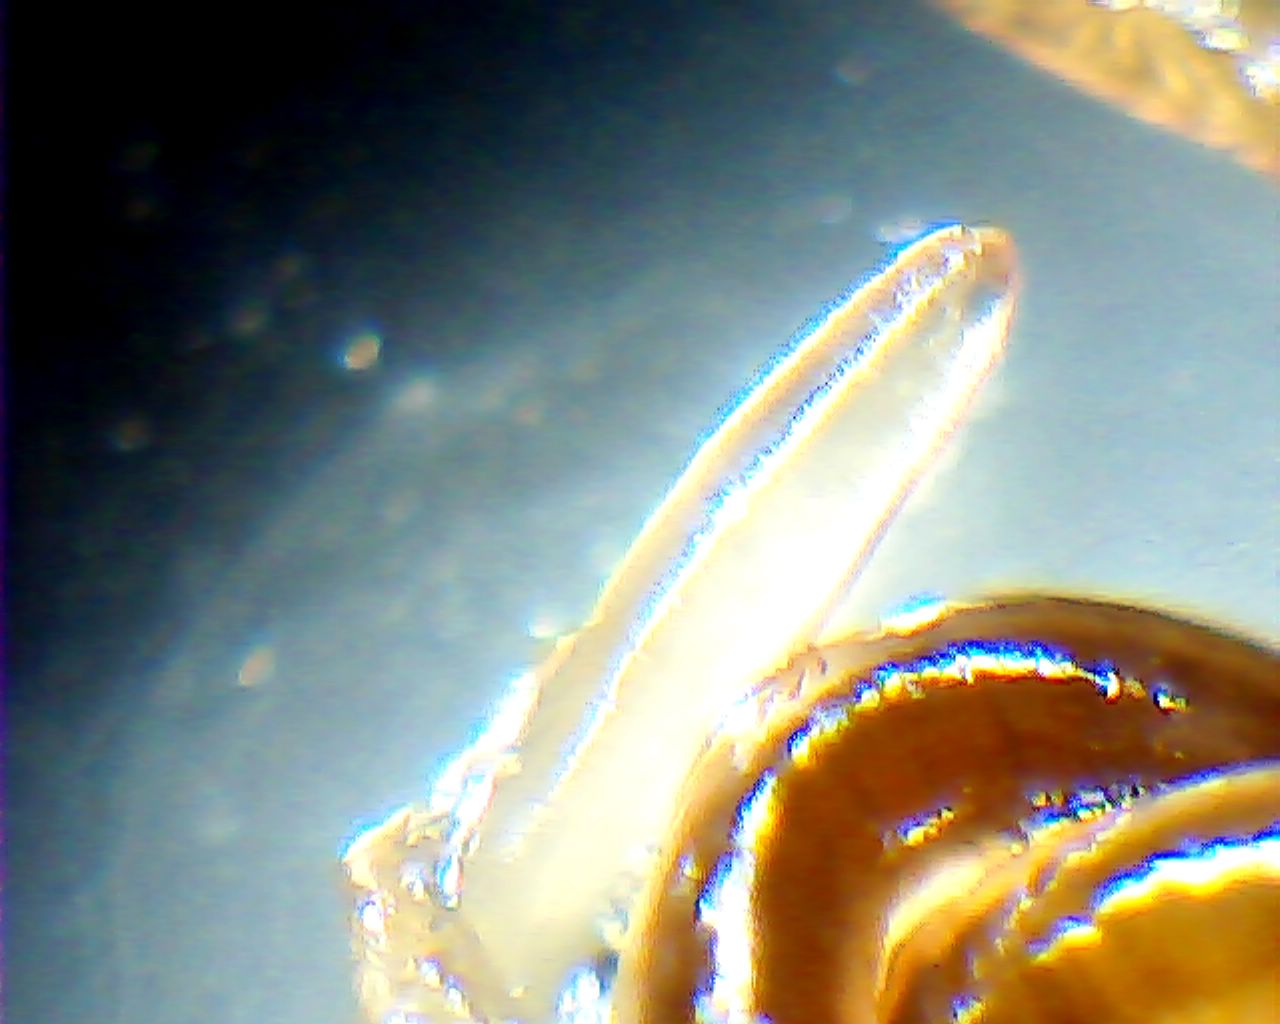

Червяк-паразит Eustrongylides excisus под микроскопом.

– Ещё осенью 2012 года я услышал, что в мясе хищной рыбы, которую выловили в плавнях, появились новые паразиты, – рассказал Владимир Никифоров, – я попросил всех коллег, если они поймают рыбу – дать на исследование. В марте мне принесли десяток окуней. В каждой рыбине было от 5 до 35 слизистых капсул – личиночная стадия червя. Они распологались по всей длине окуней.

По словам Владимира Никифорова, он проконсультировался со многими учёными из Украины и России и сделал вывод, что обнаруженный червь-паразит является Eustrongylides excisus. Его уже обнаружили в Волге и, скорее всего, он был принесён оттуда цаплями.

– Среди местных рыбаков существует мнение, что зараженную этим паразитом рыбу можно есть, – говорит учёный, – но их российские коллеги утверждают, что личинки нематод из семейства Dioctophymidae (в том числе паразит, обнаруженный в кременчугской рыбе – ред.) опасны для здоровья человека и животных. При попадании в организм у человека наблюдается картина, похожая на пиелонефрит, цистит или уретрит.

– Чтобы безопасно есть днепровскую рыбу, её нужно поддать термической обработке в течение не менее 20 минут, – говорит доктор наук, – но после этого не многие захотят эту рыбу есть. К тому же, вы получите мало удовольствия, когда почувствуете на зубах слизистую капсулу, раскусив которую у вас во рту окажется несколько червячков.

Высохшая капсула от яйца паразита и высохшие «молодые» червяки.